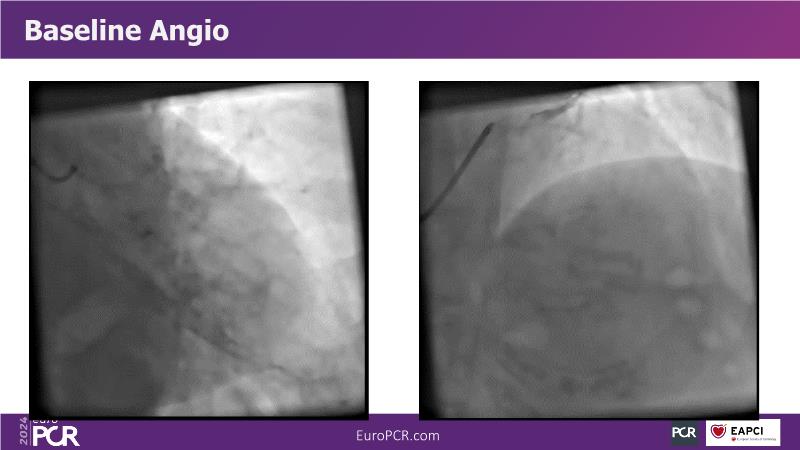

Discover the remarkable performance of Supraflex Cruz in real-world clinical settings, showcasing exceptionally low event rates and demonstrating its safety and efficacy across a spectrum of high-risk patients, including the elderly and those with high bleeding risks, and delve into the ongoing TALENT and TUDEXO II trials, designed to further elucidate the benefits of employing best PCI practices, particularly focusing on the efficacy of ultrathin struts such as Supraflex Cruz in managing complex CAD, including three-vessel disease, especially in diabetic populations.